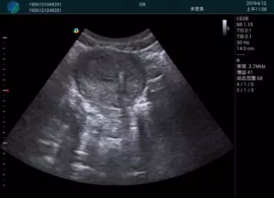

病例二:

腺體內(nèi)部清晰顯示一低回聲塊影,形態(tài)不規(guī)則,邊界模糊,邊緣呈毛刺狀,內(nèi)部見砂礫樣鈣化

M20引導(dǎo)下穿刺活檢術(shù)

M20引導(dǎo)下平面內(nèi)穿刺取出的腫塊組織

M20查看:囊內(nèi)回聲均勻,邊界清晰,囊壁光滑

M20引導(dǎo)抽吸術(shù)后囊腫消失,原區(qū)域空腔形成,脂肪層與腺體層架構(gòu)發(fā)生改變

超聲以操作簡單、定位準確、實時顯像、費用低廉等優(yōu)勢,而成為麥默通乳腺活檢治療乳腺腫塊最常見的引導(dǎo)手段,已逐步在各大醫(yī)院開展此類手術(shù)。

2、超聲的可視化操作,能準確的顯示病灶的位置、最大徑,選擇合適的刀具,決定切口的位置和方向,避開血管、減少出血危險并實時觀察乳腺病灶的切割情況,避免造成腫塊組織殘留